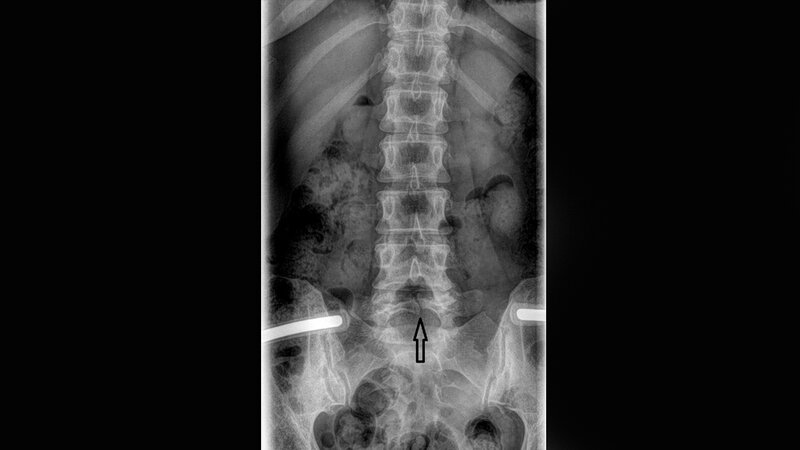

Die Spina bifida ist eine angeborene Veränderung mit inkomplettem Verschluss der Wirbelsäule, bedingt durch einen knöchernen Defekt, in der Mittellinie des Wirbelbogens gelegen. Die Patienten mit Spina bifida occulta sind meist asymptomatisch ohne künftige Verschlechterung des Status und brauchen keine Therapie.

Spina bifida is a congenital disorder with incomplete closure of the spinal column due to a bony vertebral defect. Spina bifida occulta is characterized by a bony defect of the vertebral arch. The patients with spina bifida occulta are often asymptomatic with no future complications and do not require treatments.